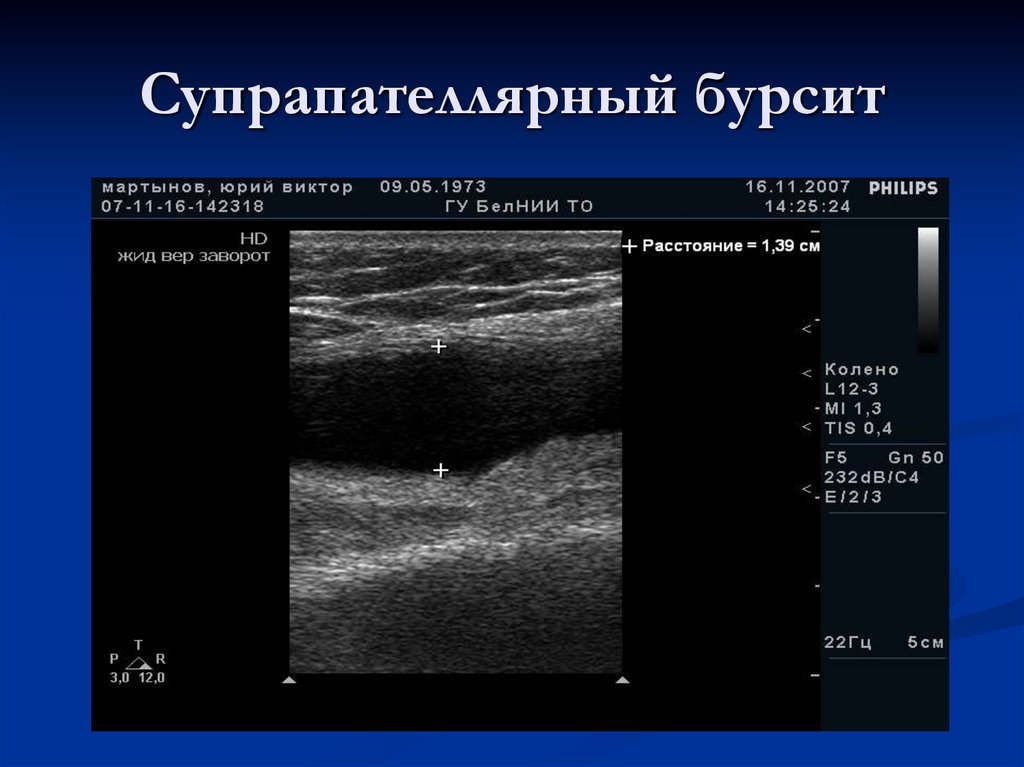

Супрапателлярный бурсит

Преднадколенниковая сумка – Bursa prepatellaris